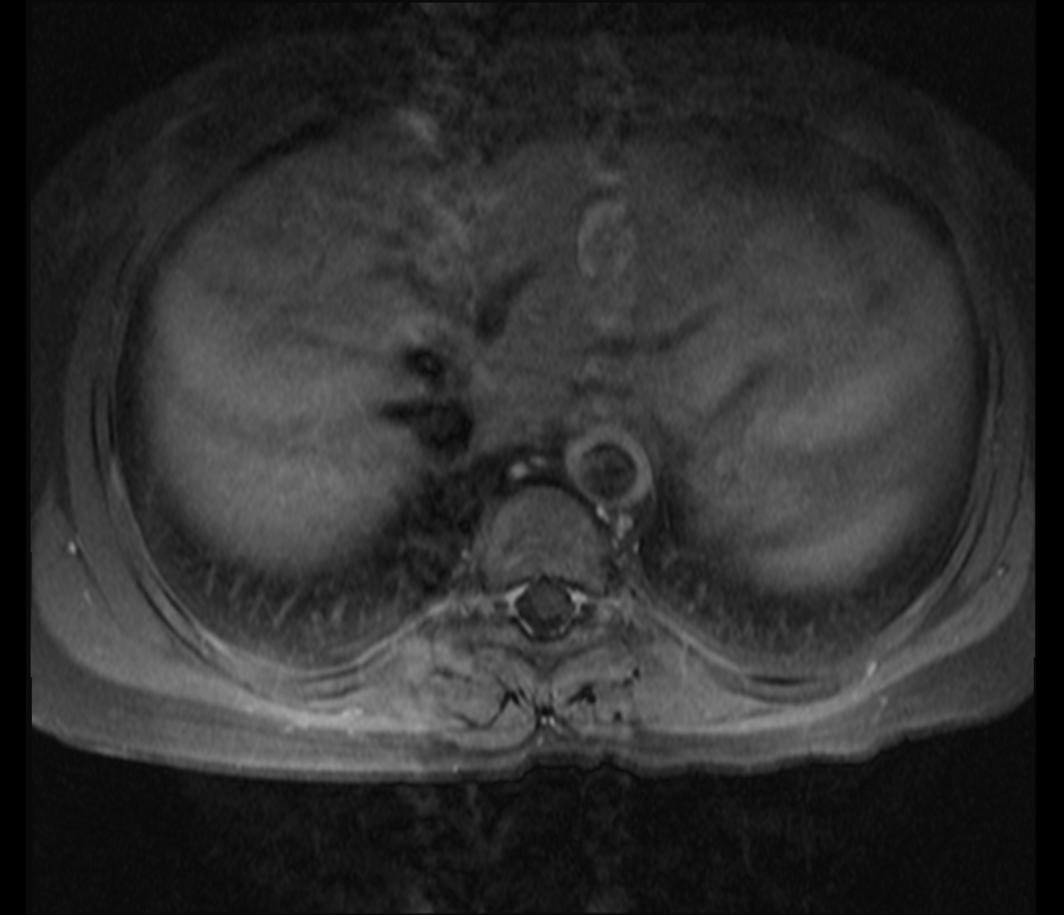

- CT, MRI: 조영제를 사용한 검사는 본증 진단에 매우 중요하며, 다이내믹 조영 기법을 통해 동맥 협착 정도를 평가할 수 있다.

- CT 혈관 조영술, MR 혈관 조영술: 조영·비조영 MRI나 조영 CT 정보를 3차원적으로 재구성한 MRA(MR 혈관 조영술) 및 CTA(CT 혈관 조영술)는 혈관 조영술보다 정밀도는 떨어지지만 유사한 정보를 제공한다.